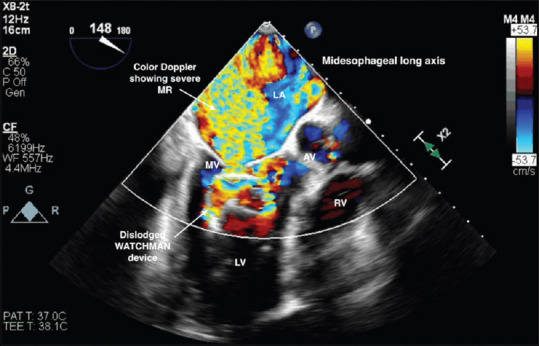

Abstract: WATCHMAN (Boston Scientific, Plymouth, MN, USA) is the most commonly utilized left atrial appendage occlusion device. Although increased operator experience has led to a significant decline in reported complications, serious and potentially fatal events can still occur. We present a case of WATCHMAN device embolization that was identified using transesophageal echocardiography shortly after device deployment, along with the subsequent management and retrieval of the device.